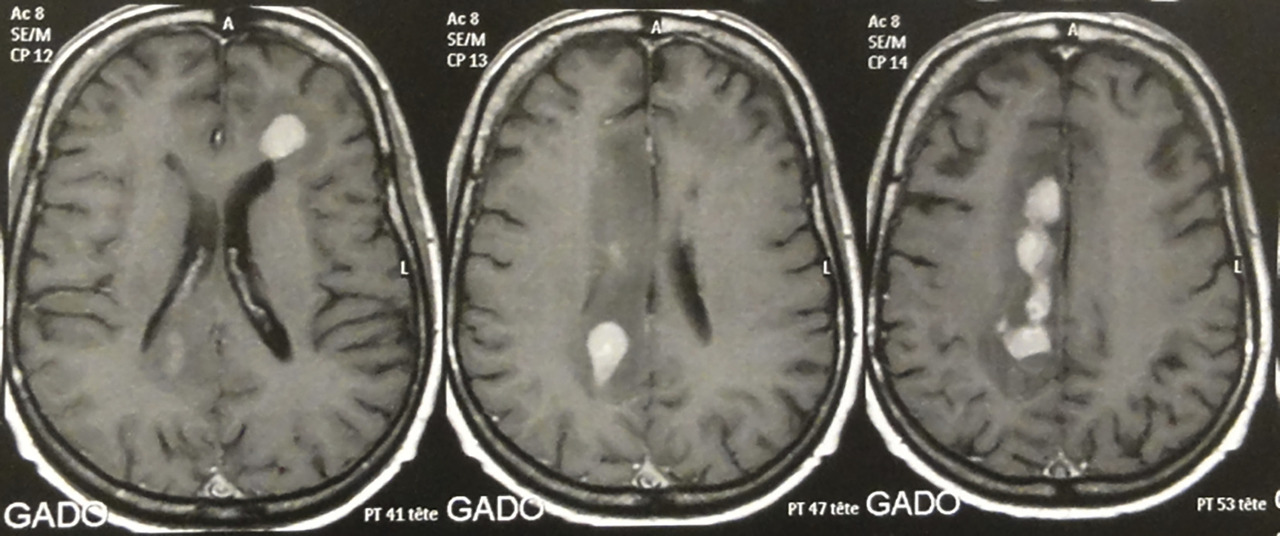

Les LNH du système nerveux central (SNC) représentent environ 1 % des LNH chez les patients immunocompétents. Ils touchent le parenchyme cérébral, le liquide céphalorachidien (méningite lymphomateuse) et l’œil. Ainsi, le bilan doit systématiquement comporter, en plus du TEP-scanner, une IRM cérébrale, une ponction lombaire (PL) en l’absence de contre-indication, et un examen ophtalmologique. Ils ont rarement une localisation systémique (hors SNC) associée.

Sur l’IRM, les lésions lymphomateuses prennent le gadolinium et se situent le plus souvent près des ventricules (fig. 4). Le diagnostic repose sur une biopsie stéréotaxique.